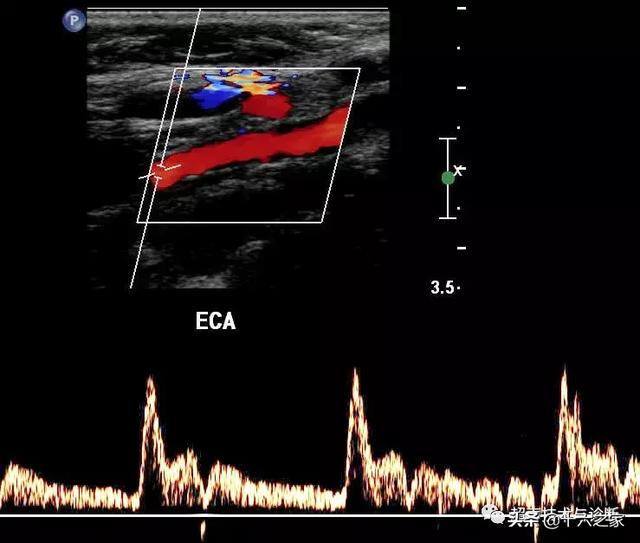

血管超声超声如何辨别颈内动脉与颈外动脉

图片尺寸640x543